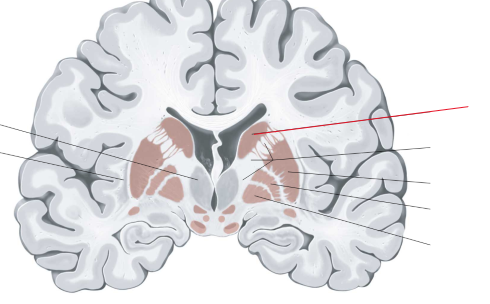

nucleus caudatus

putamen

globus pallidus

capsula interna (corona radiata)

capsula externa

capsula extrema

hippocampus

amygdala

laterale ventrikels (I en II)